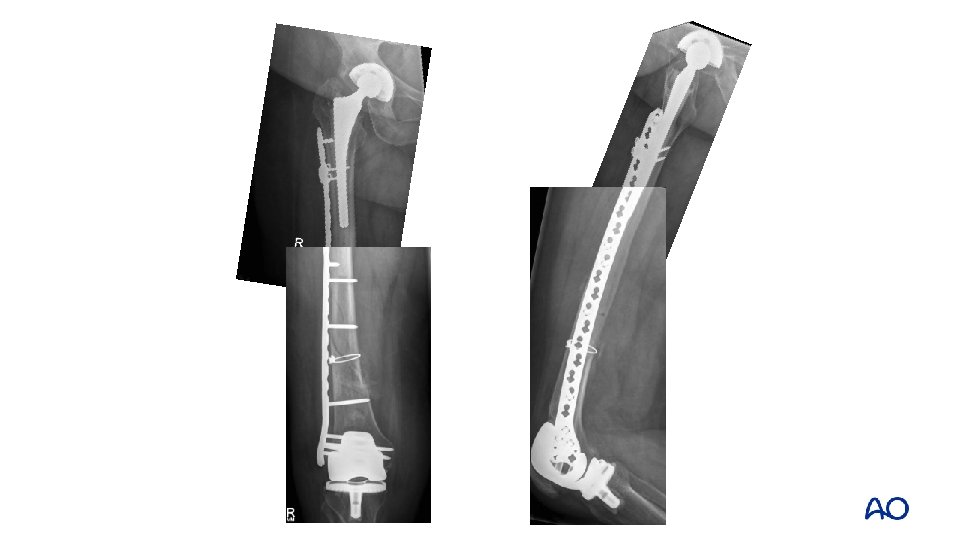

Type C: fix the fracture • • Osteoporotic bone • IM fixation • Fixed-angle device • Locking plates • DCS • Blade plate Poor biology (age, illness) • Minimize stripping • Consider augmentation with strut

• Open reduction of fracture with cerclage fixation • Positioning and fixation of plate

• IV. 3 -D: intercalary close to THA • Use of cerclage wire • Either to facilitate reduction • Or improve fixation around the femur